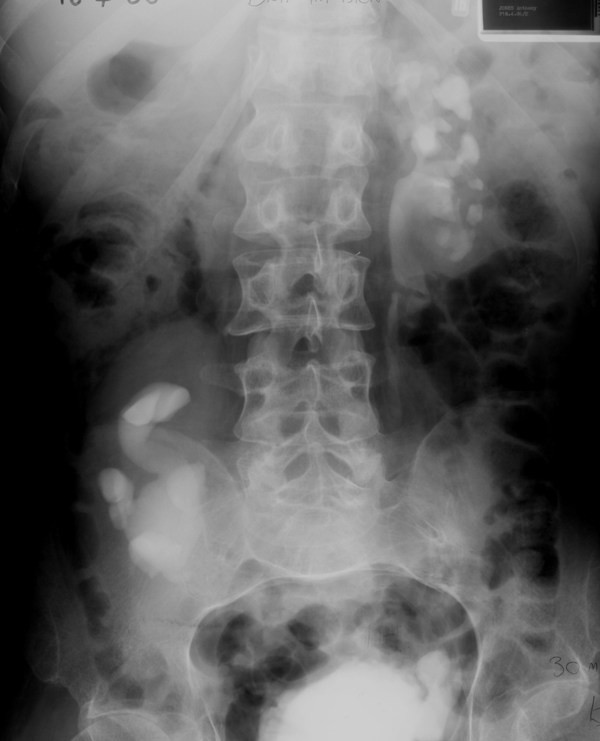

Figure 2From: Lessons we learn from review of urological procedures performed during three decades in a spinal cord injury patient: a case reportDrip infusion pyelography (18 April 1986) shows clubbing of calyces and thinning of left renal cortex. There is dilatation of the pelvicalyceal system in the malrotated right kidney.Back to article page